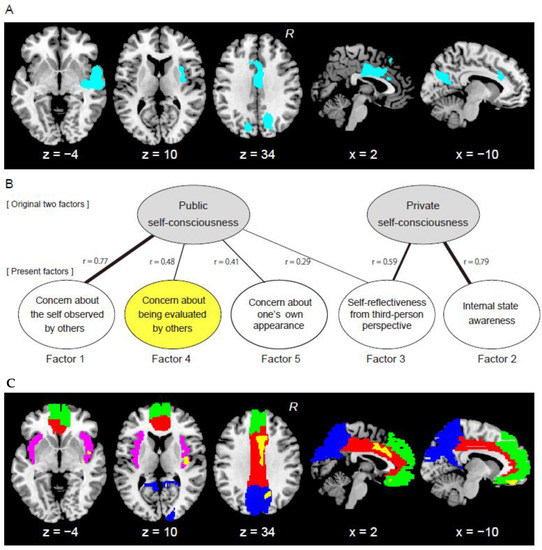

3.1. Results from Whole-Brain Analysis

3.2. Results from Factor Analysis

3.3. Results from ROI Analysis

| Clusters | Number of Voxels | Cluster-Level p (Corrected) | MNI Coordinates | T-Value | Anatomical Identification (Cytoarchitectonic Map) | ||

|---|---|---|---|---|---|---|---|

| x | y | z | |||||

| Cingulate cluster | 2172 | 0.03 | 3 | −2 | 33 | 3.94 | Rt MCC |

| −12 | 24 | 32 | 3.27 | Lt MCC | |||

| 0 | 27 | 50 | 3.09 | Superior medial gyrus | |||

| −6 | 27 | 24 | 3.02 | Lt ACC | |||

| 2 | 26 | 23 | 2.98 | Rt ACC | |||

| Rt temporal cluster | 4206 | <0.001 | 56 | −6 | −3 | 4.77 | Superior temporal gyrus (Area TE 1.2) |

| 50 | −17 | 0 | 4.34 | Superior temporal gyrus | |||

| 56 | 8 | −8 | 4.13 | Temporal pole (Area TE 3) | |||

| 42 | −20 | −6 | 3.90 | Insula (Area Id1) | |||

| 57 | −20 | −11 | 3.67 | Middle temporal gyrus | |||

| 33 | −3 | 14 | 3.47 | Insula | |||

| 35 | −14 | −3 | 3.45 | Insula (Area Ig2) | |||

| 53 | 8 | −30 | 2.92 | Temporal pole | |||

| Rt precuneus cluster | 2359 | 0.02 | 17 | −75 | 27 | 4.27 | Cuneus |

| 11 | −53 | 23 | 4.19 | Precuneus | |||

| 24 | −69 | 23 | 4.02 | Superior occipital gyrus | |||

| Lt precuneus cluster | 1859 | 0.06 | −15 | −57 | 26 | 4.40 | Cuneus |

| −17 | −68 | 30 | 4.07 | Superior occipital gyrus | |||

| −14 | −53 | 18 | 3.60 | Precuneus | |||

| ROIs | Number of Voxels | Cluster-Level p-Value (Corrected) | MNI Coordinates | T-Value | ||

|---|---|---|---|---|---|---|

| x | y | z | ||||

| Brain regions with gray-matter expansions in individuals with high scores on Factor4 | ||||||

| ACC/MCC | 1342 | 0.01 | 11 | 20 | 26 | 3.74 |

| Insula | 534 | 0.07 | 41 | −14 | 3 | 3.55 |

| Precuneus/cuneus | 1080 | 0.03 | 12 | −48 | 20 | 4.12 |

| MPFC | 633 | 0.08 | −5 | 42 | −21 | 3.82 |